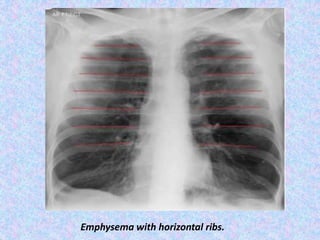

Emphysema with horizontal ribs.